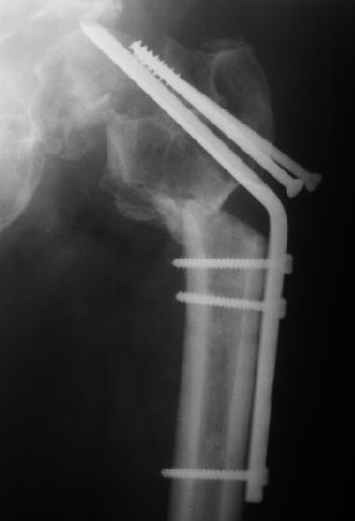

Мужчину 56 лет оперировали у нас в августе 2003 г. - вальгизируюшая остеотомия из-за позднего (через 2 мес. после травмы) поступления с переломом шейки бедра (картинки 1,2). Курильщик, соматической патологии не было. Сейчас поступил с жалобами на проблемы в области тазобедренного сустава, на снимках 3,4 видно вырезывание клинка.Чтоб можно посоветовать в этой ситуации? Заранее спасибо.

A male 56 years old was operated in Aug 2003 - valgus osteotomy performed because of delayed admission with neck fracture (2 months) images 1,2. Smoker, no other major medical problem. Now he re-admitted with the images 3,4.What would you do in the situation?THX in advance.